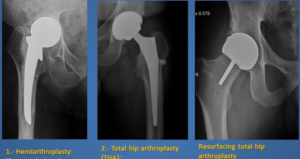

الابتكار في المواد الحيوية مثل البولي إيثيلين المشبع بفيتامين E ـ (Vitamin E-infused HXLPE) أحدث ثورة في عمر المفاصل الافتراضي.

يشدد الخبراء على أن المستقبل يكمن في استخدام السجلات الوطنية للمفاصل وتحليل البيانات لتحسين جودة العمليات.

استخدام التقنيات الرقمية في التخطيط قبل الجراحة يقلل من نسبة الخطأ البشري.